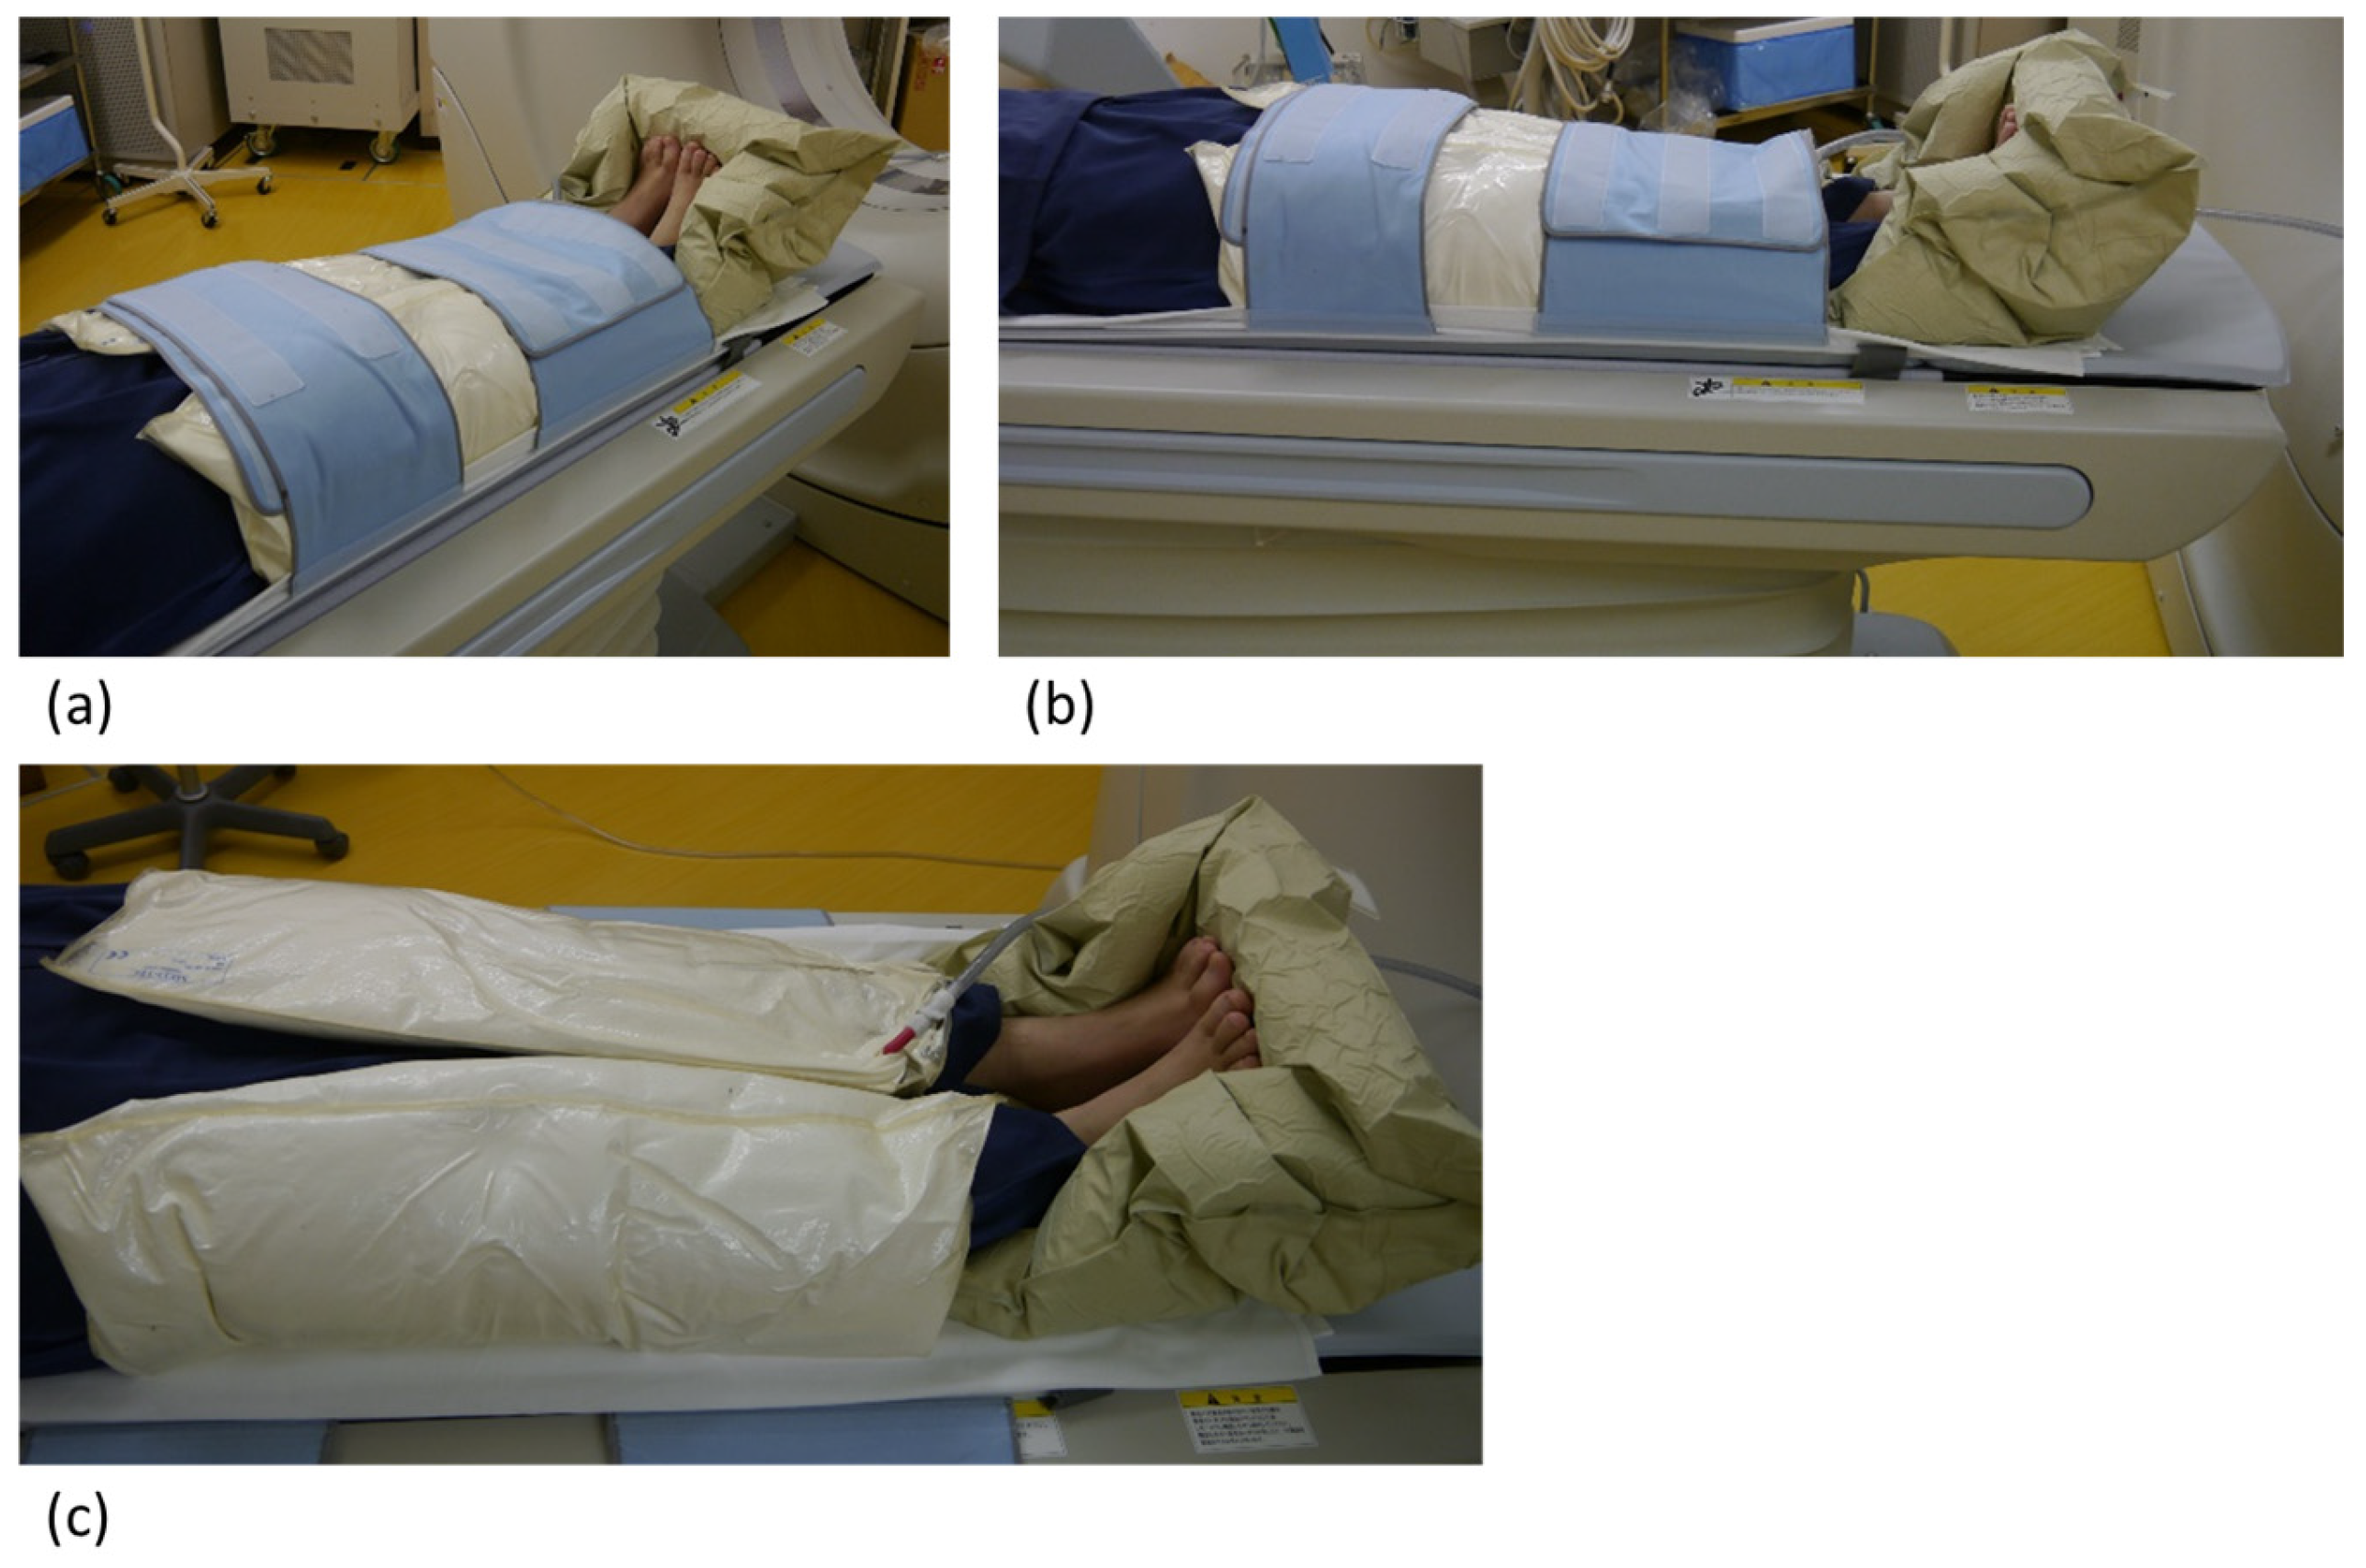

2.2. CT Angiography